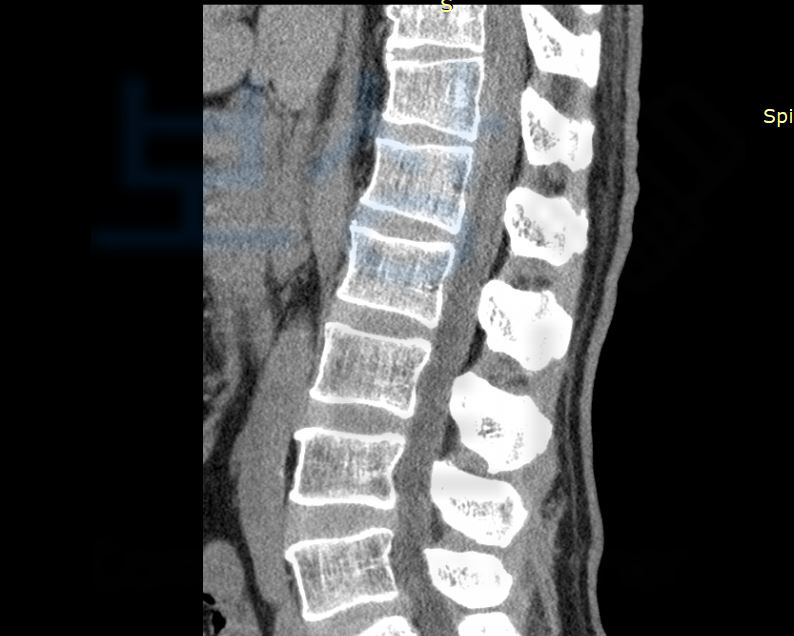

흉추11번, 흉추12번 골절

권@@님은 척추보조기 (TLSO)를 착용하시며 전치8주 즉 8주간의 안정을 취하셔야 했습니다. 권@@님은 사고 초기부터 보상파트너에 연락주셔서 함께 보험증권과 사고경위, 영상CD를 보고 상담을 도와드렸습니다.

뿐만 아니라 허리 골절, 즉 흉추 골절은 골절진단비,실비,입원비 뿐만 아니라 후유장해보험금도 확인하셔야 합니다. 저희는 보상 가능성을 확인해

척추의 뚜렷한 기형을 남긴 때 30%의 지급률을 모두 인정받게 되어 1억의 30% ,3,000만원의 보상 받으셨습니다. 권@@님의 경우 교통사고 전치8주 합의금과 개인보험의 장해 보상으로 총 6,500만원의 보상 받으신거죠.